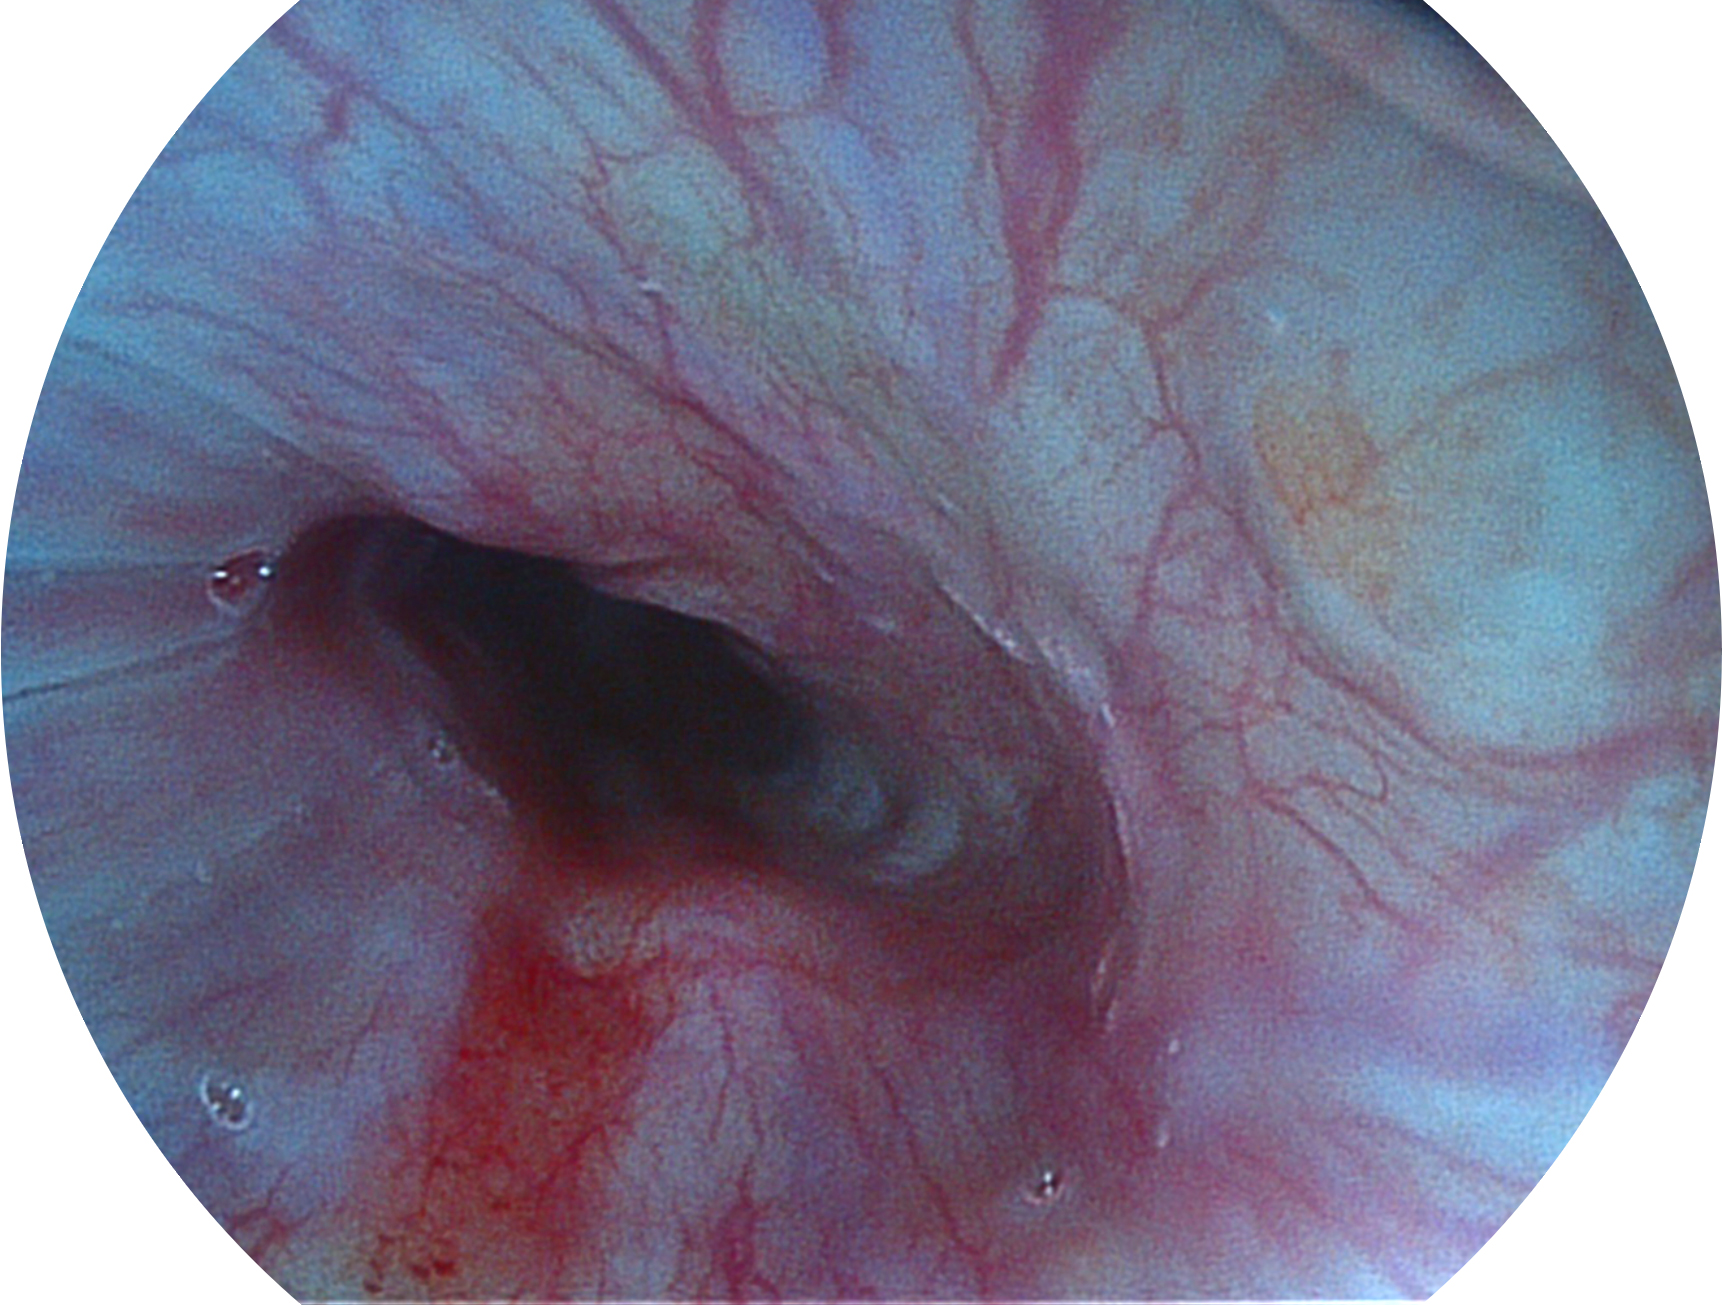

SFI技術(shù)是結(jié)合特定光譜照明與數(shù)字光譜濾波,實(shí)現(xiàn)高亮度特殊光成像。染色模式下,不改變粘液、食物殘?jiān)?、糞液等基本顏色,在保持與白光照明相似的圖像色調(diào)的同時(shí)突顯了圖像顏色的紅白對比度,且在遠(yuǎn)距離觀察的情況下具備與普通白光模式相同的圖像亮度,有助于消化道疾病的大范圍掃查和早癌篩查。

• 白光圖像 SFI圖像